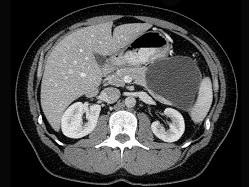

问题 关于假性胰腺囊肿,下列哪项是错误的 ( )

选项 A、可形成脓肿 B、继发于胰腺或上腹部外伤后 C、可形成胰源性腹水 D、无上皮细胞 E、多位于胰头部

答案 E